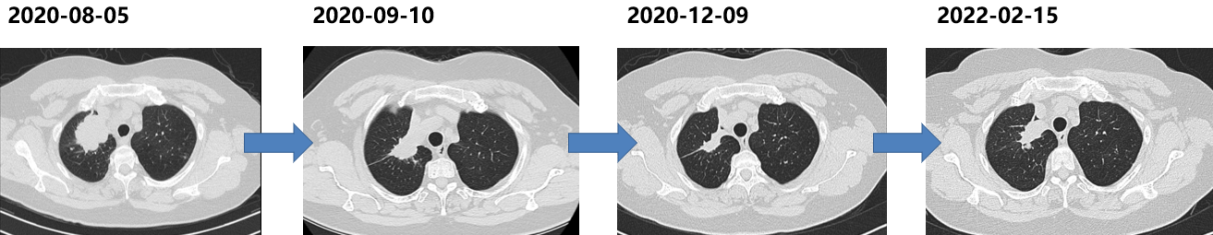

一线治疗(2020-08至2022-02)

方案:奥希替尼80mg QD

疗效评价:PR

PFS:18个月

胸部CT(2022-02):右上肺病灶较前增大,肺内转移灶进展。

二线治疗(2022-02至2024-01)

依据:耐药机制不明,参考ORIENT-31研究模式。

方案:

诱导期:PD-1单抗+贝伐珠单抗+培美曲塞+卡铂,共6周期。

维持期:PD-1单抗+贝伐珠单抗+培美曲塞。

PFS:23个月。

胸部CT(2024-01-31):肺部病灶进展。